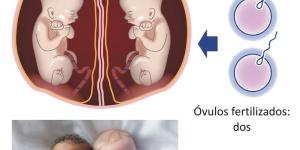

Los embarazos gemelares son todo un acontecimiento para la familia, y es que tener dos fetos creciendo al mismo tiempo y que nacerán en el mismo parto es una situación emocionante que, al mismo tiempo, puede generar algo de ansiedad en los padres.

Se entiende por gemelo a dos cigotos cuya gestación y desarrollo...